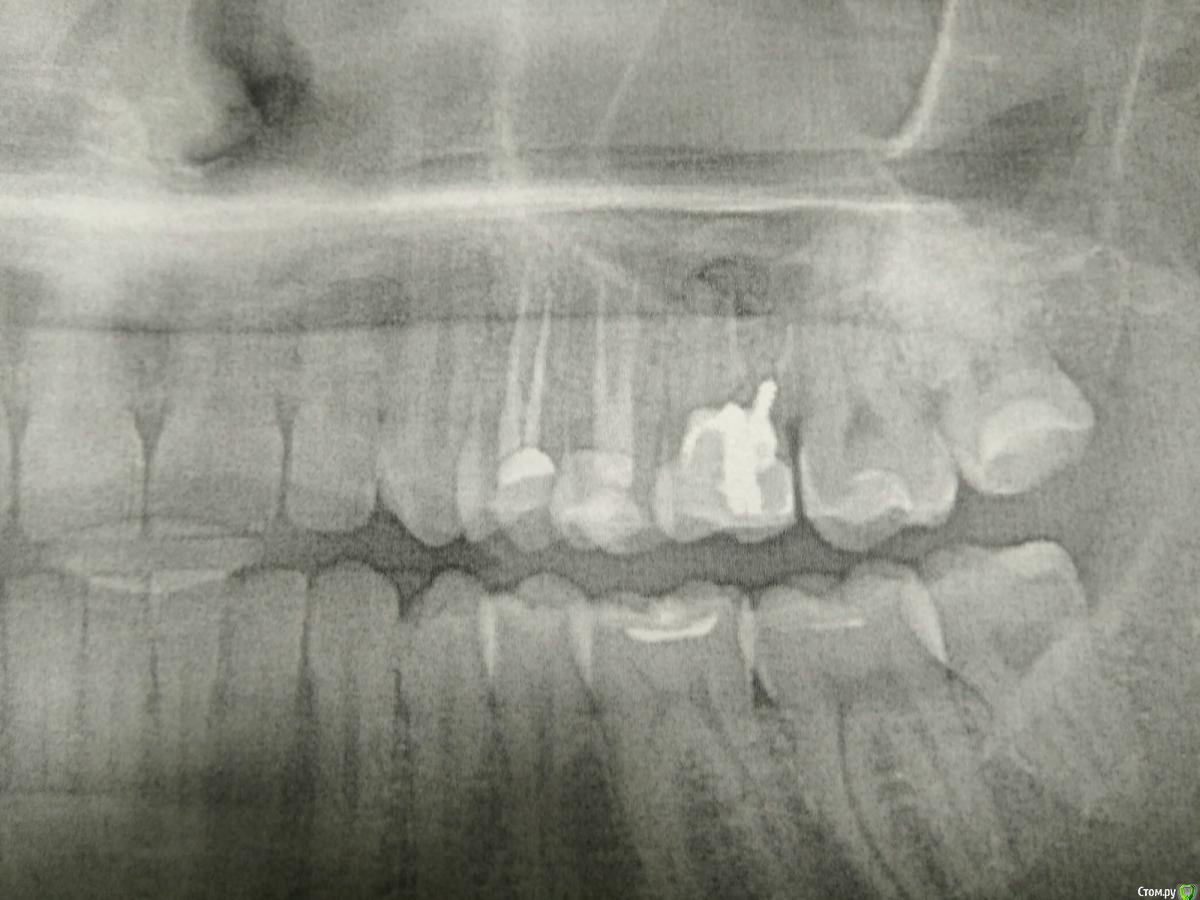

со слов стоматолога: зуб шестёрка (на снимке сверху справа) - стоит непонятная полу-коронка со штифтом, каналы не были заделаны (правильно?), рассасывание костной ткани, хроническое воспаление, рядом пазуха и есть щели с соседними зубами 5, 7.

Зуб 6 делали несколько лет назад.